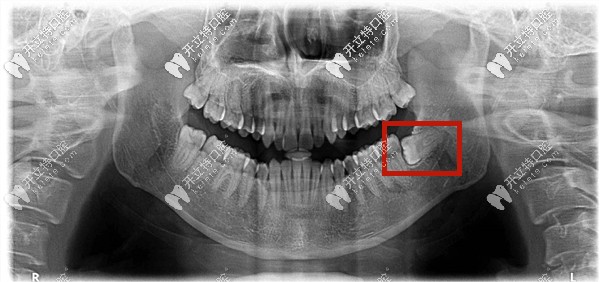

下頜低位阻生智齒圖片

低位阻生齒——就是牙的高處部位低于第二磨牙的牙頸部,它可以是近中低位,垂直低位,遠(yuǎn)中低位等,也有可能牙全部被包埋在牙骨內(nèi),所以又稱之為骨埋伏阻生智齒。

這種情況下的智齒一般從口中看不到,需要拍片才能確定。